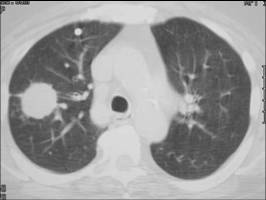

Malignant

Lobulated

Spiculated

Irregular